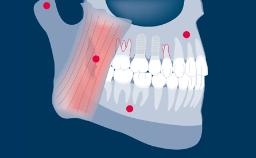

Independentemente da localização ou extensão do tratamento, o planejamento da terapia com implantes deve ser sempre orientado pela prótese. Isso garante que a instalação do implante atenderá às necessidades protéticas e será compatível com o resultado final desejado. Com o objetivo de alcançar um resultado ideal, o planejamento protético deve considerar todos os fatores protéticos relevantes e um modelo diagnóstico adequado como base para o planejamento específico das próteses sobre implante e implantes de suporte.

- discutir considerações gerais de planejamento protético relacionadas à terapia com implantes

- delinear os pontos de planejamento específicos para próteses sobre implante e seus implantes de suporte